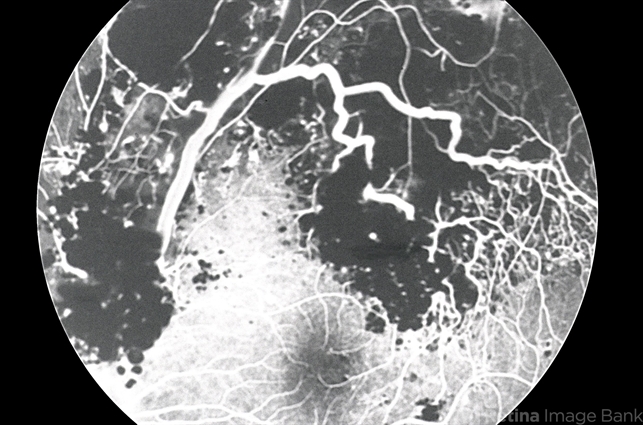

- cavernous hemangioma of the retina

- Fluorescein angiogram of retinal cavernous hemangioma shows slow filling with early blocked fluorescence #1.